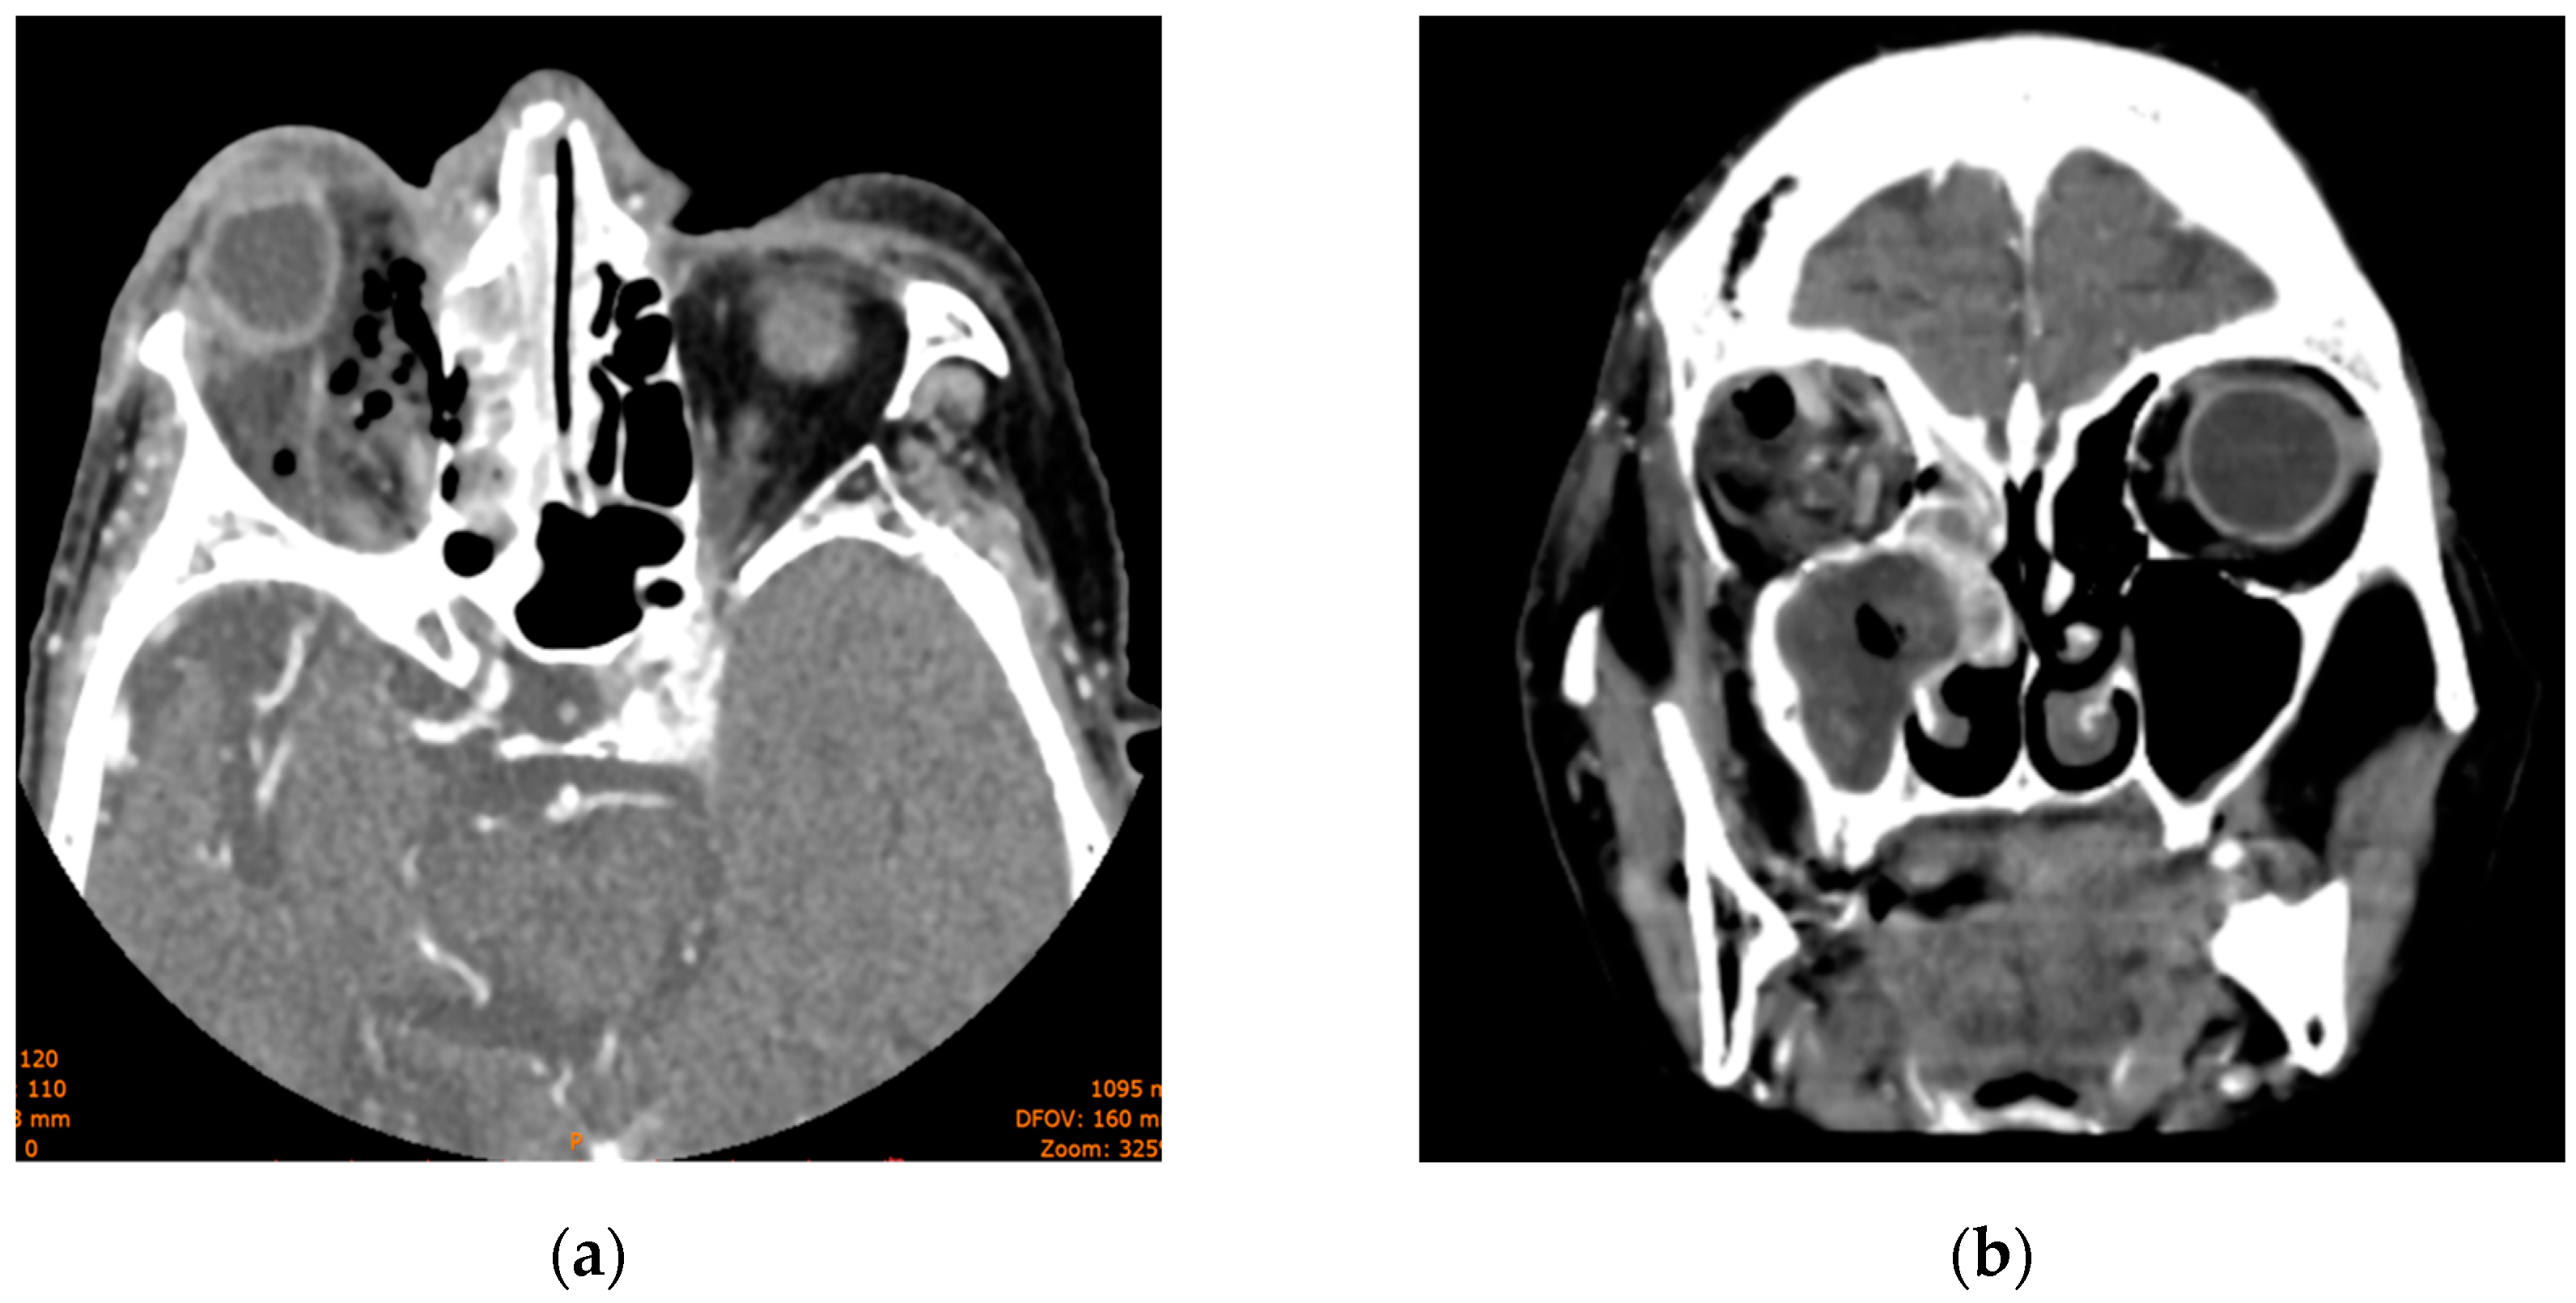

2. Case 1

3. Case 2